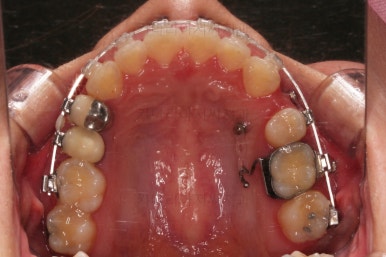

초진 시 입안의 모습을 보실게요.

결국은 앞니 사이에 틈이 생겼기 때문에 이같은 문제점을 인지하시고 내원하셨던거죠.

우선 장치를 부착했습니다.

이번에 선택한 장치는 엠파워 클리어라고 하는 자가결찰 세라믹 장치인데요.

흔히 아시는 클리피씨 장치와 같은 분류의 장치입니다. 클리피는 일본, 엠파워는 미국 제조사라는 차이가 있지만 큰 틀에서는 세라믹 바디에 금속 클립이 달린 거의 동일한 장치라고 보시면 됩니다.

장치 부착 직후의 모습인데요.

장치가 보이는 느낌이나 옆라인의 변화 양상은 참고해 주세요.